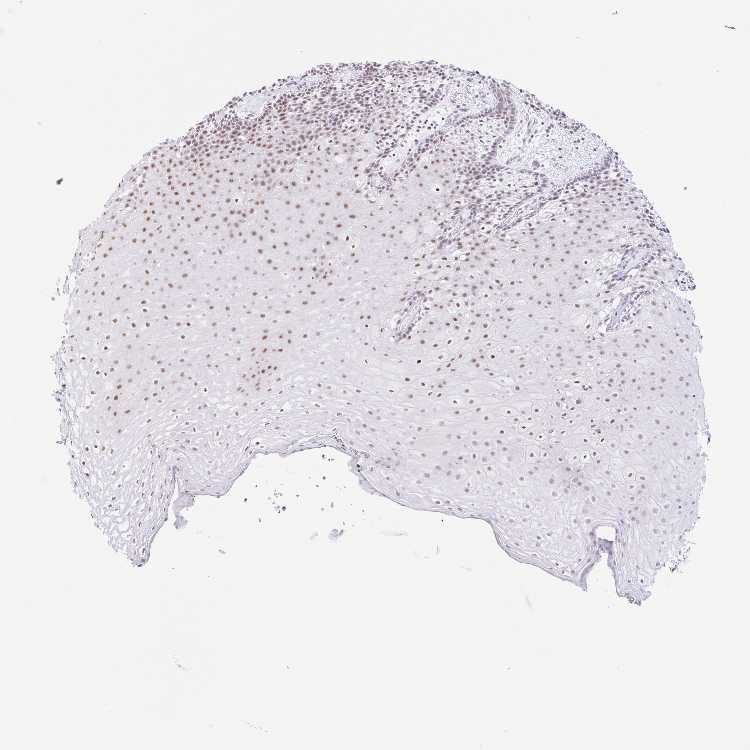

TISSUE PRIMARY DATA ORAL MUCOSA Show tissue menu

ORAL MUCOSA - Antibody stainingi

Antibody staining in the annotated cell types in the current human tissue is reported as not detected, low, medium, or high, based on conventional immunohistochemistry profiling in selected tissues. This score is based on the combination of the staining intensity and fraction of stained cells.

Each image is clickable and will lead to virtual microscopy that enables deeper exploration of all samples and also displays staining intensity scores, fraction scores and subcellular localization as well as patient and tissue information for each sample.

Antibody HPA056814

Squamous epithelial cells Medium